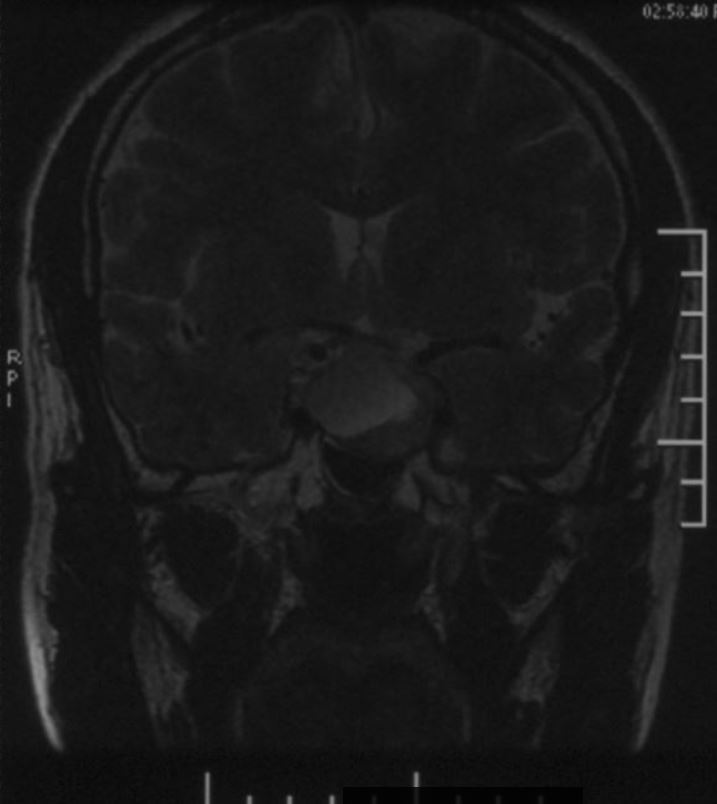

鞍区磁共振检查发现:鞍区肿瘤卒中可能,肿瘤侵犯双侧海绵窦、颈内动脉,鞍隔被顶起,鞍底部分塌陷。

冠状位增强